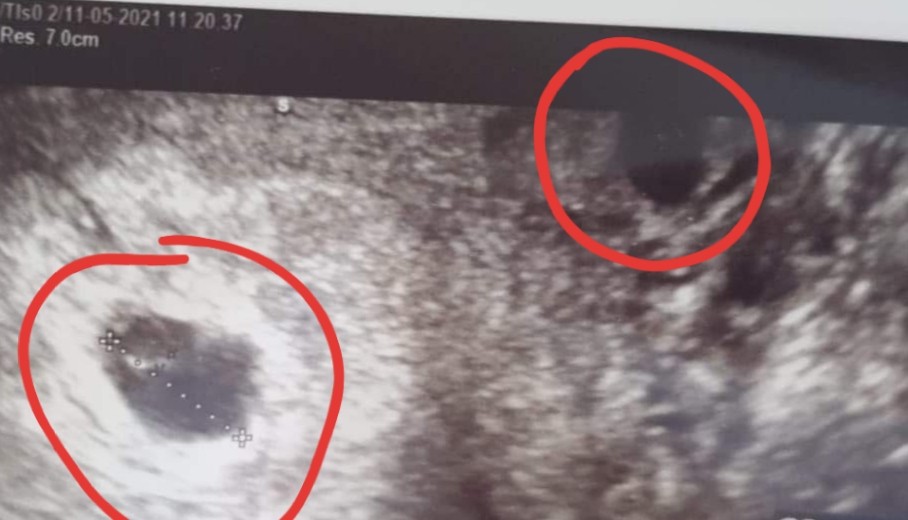

Hej Mamusie bliźniaków. Pierwsze usgz 5 tyg ciazy drugie z 6 tygodnia ciazy. Czy to są 2 pęcherzyki ciążowe? Czy mam jakieś urojenia? Lekarz nic nie mówił Ale za to przepisał duphastpn i luteine A przy pierwszej ciazy tylko luteine. Dziękuję Wam za odpowiedź. Może pamiętacie swoje usg z początków. :D

Załączniki

• 20210512_155147.jpg

20210512_155147.jpg

176,2 KB · Wyświetleń: 114

• 20210512_155115.jpg

20210512_155115.jpg

74,6 KB · Wyświetleń: 105